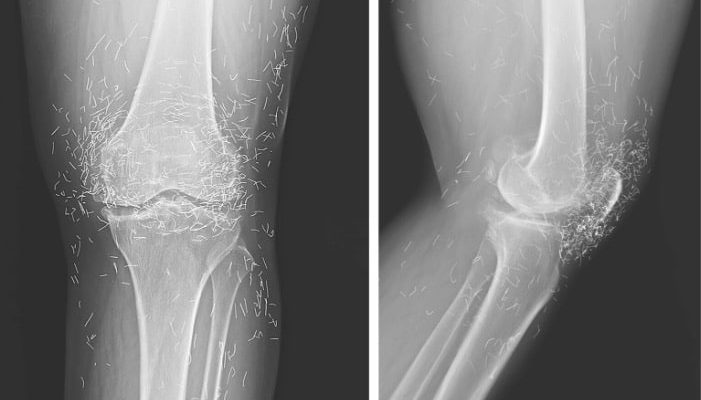

Years later, when doctors took X-rays to evaluate her knee condition, they weren’t prepared for what appeared on the images. Her knees were filled with dozens of bright, metallic flecks — tiny needles embedded deep within the joint area.

The findings were later documented in a case published by the New England Journal of Medicine.

Beyond inflammation, the needles created another problem: imaging complications. Metal objects can obscure parts of the anatomy on X-rays, making it harder for doctors to clearly assess joint damage or disease progression.